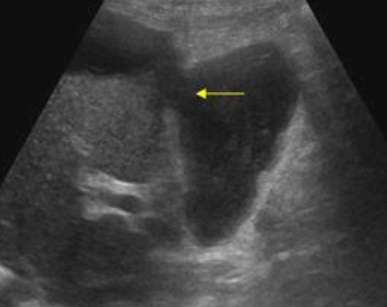

US finding

- 불규칙하고 불분명한 담낭벽 비후

- 담낭비대

- 담석